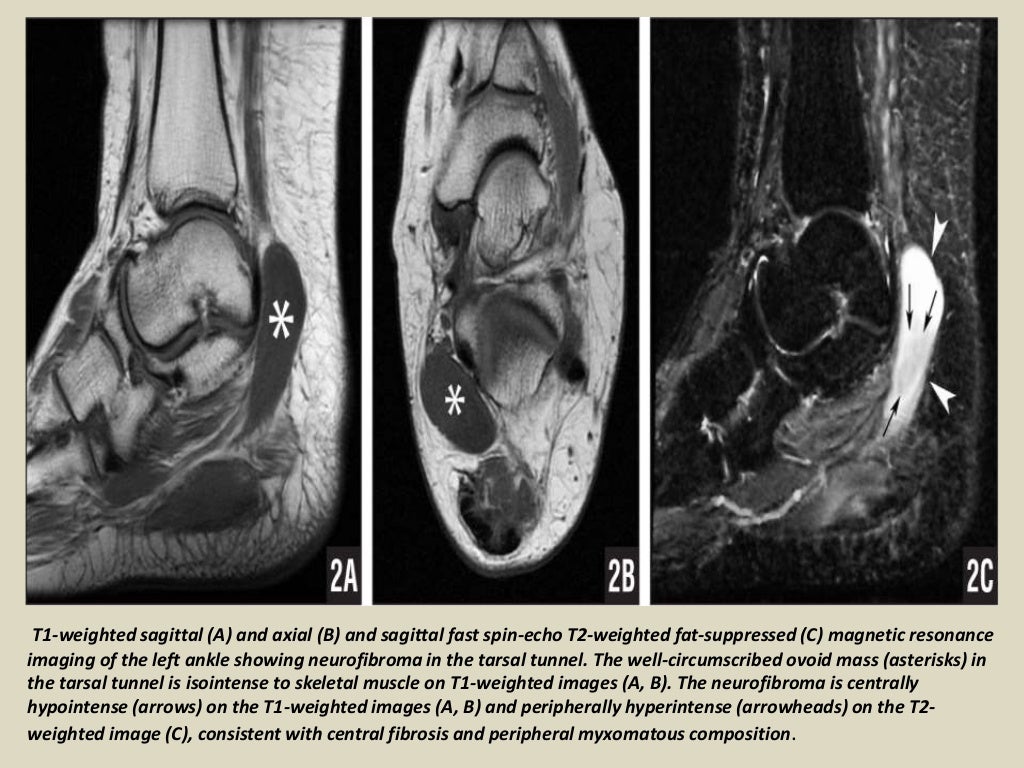

Presentation1 radiological imaging of tarsal tunnel syndrome.

Presentation1 radiological imaging of tarsal tunnel syndrome. Tarsal Tunnel Syndrome X Ray Tarsal tunnel syndrome refers to an entrapment neuropathy (tunnel syndrome) of the (posterior) tibial nerve or of its branches within the tarsal tunnel. Tarsal tunnel syndrome refers to an entrapment neuropathy (tunnel syndrome) of the (posterior) tibial nerve or of its branches within. Mr imaging can accurately depict the contents of the tarsal tunnel and the courses of the terminal. Tarsal Tunnel Syndrome X Ray.

Presentation1 radiological imaging of tarsal tunnel syndrome. Tarsal Tunnel Syndrome X Ray This condition is analogous to carpal tunnel. Tarsal tunnel syndrome is a compressive neuropathy of the tibial nerve at the level of the tarsal tunnel which can lead to pain. Tarsal tunnel syndrome (tts) is a common entrapment syndrome whose diagnosis can be difficult. Tarsal tunnel syndrome refers to an entrapment neuropathy (tunnel syndrome) of the (posterior) tibial nerve or. Tarsal Tunnel Syndrome X Ray.

Presentation1 radiological imaging of tarsal tunnel syndrome. Tarsal Tunnel Syndrome X Ray This condition is analogous to carpal tunnel. Tarsal tunnel syndrome is a compressive neuropathy of the tibial nerve at the level of the tarsal tunnel which can lead to pain. Tarsal tunnel syndrome refers to an entrapment neuropathy (tunnel syndrome) of the (posterior) tibial nerve or of its branches within the tarsal tunnel. Tarsal tunnel syndrome refers to an entrapment. Tarsal Tunnel Syndrome X Ray.